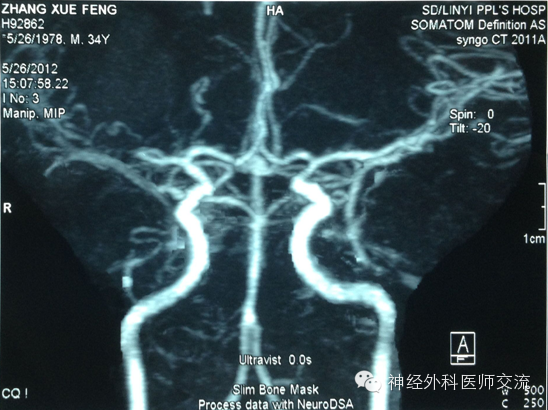

(2)CT图片处理——穿刺点的选择及介入手术入路

① 确定穿刺平面:据CT所显示的血肿,选择血肿最大断层,即为要穿刺的平面,也就是说:操作时要将引流导管沿着这一血肿最大层面进入血肿腔内。确定该层面至颅底层面的距离(即厚度)(X毫米:一般为50~60 mm)。

② 确定穿刺点:在血肿的最大层面上划出血肿的最大长轴线,与前额头皮的交点即为理论穿刺点,测出该点至血肿远端的距离(毫米),该数值减去5mm~10mm即为置管深度,一般为80~120mm。

确定实际穿刺点要做到两个避开:避开额窦、避开上矢状窦!实际穿刺点,一般为正中矢状线旁开15mm~20mm,内眦上方45mm~60mm的前额之交点,多为55mm。